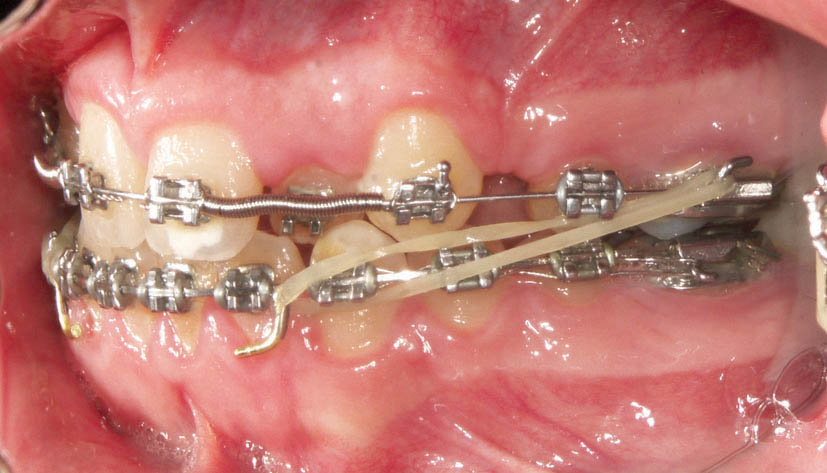

الاستیك كلاسII از هوك تیوب دندان 6 پایین به هوك آرچ وایر بالا متصل میگردد (شکل 178-1) و الاستیك كلاسIII از هوك تیوب دندان 6 بالا به هوك آرچ وایر پایین متصل میشود (شکل 179-1).

شکل 178-1: الاستیک کلاسII